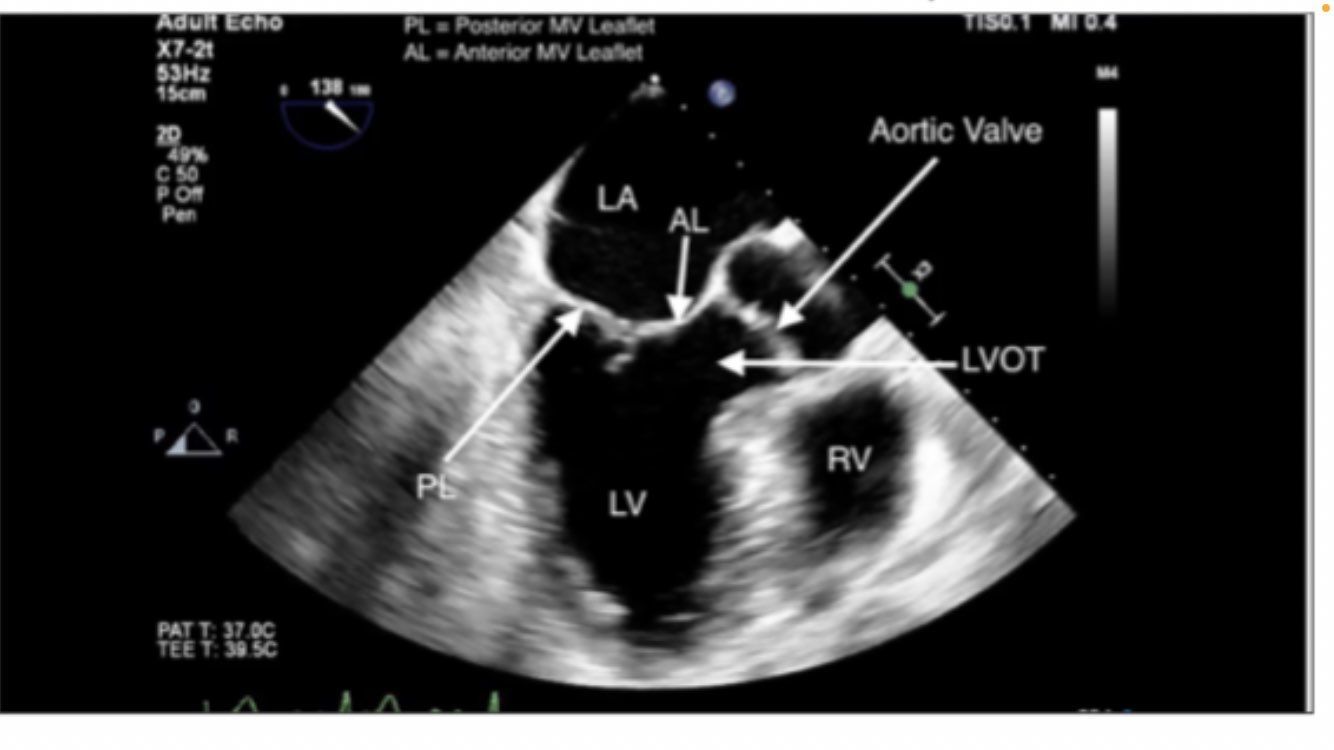

Mid-esophageal Long Axis view. LAX

midesophageal long axis